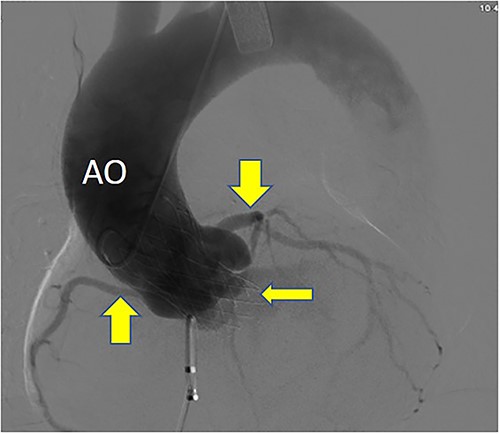

Postoperative DSA: Self-expanding valve holder’s shape and position (thin arrow) are normal, while left and right coronary artery openings (thick arrow) are unobstructed with clear blood flow.

Postoperatively, imaging studies, including TEE and digital subtraction angiography (DSA), confirmed normalization of aortic valve flow velocity and pressure gradients, with the absence of aortic regurgitation (Fig. 7). Atrial shunting disappeared, and there was no involvement of the mitral or tricuspid valves. Both the self-expanding valve prosthesis and the closure device were stably positioned, and the surgical outcome was deemed successful (Fig. 8). One month after surgery, the patient’s symptoms of chest tightness and shortness of breath had resolved.

Postoperative DSA: Digital subtraction angiography confirms the proper positioning of the aortic self-expanding valve (thin arrow) and occluder (thick arrow).